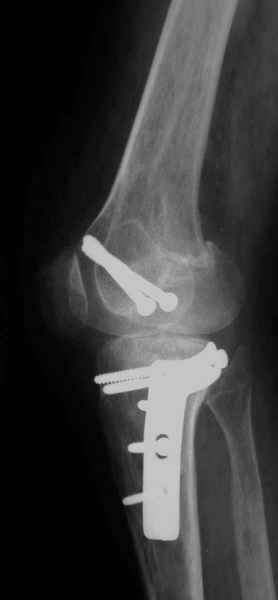

Как вариант решения прогрессирующей вальгусной деформации коленного сустава я бы предложил косую остеотомию дистального отдела бедра с фиксацией пластиной и компрессирующим винтом.

Взгляните на снимки , может быть это вам поможет.

Около 5 лет применяю этот тип дистальной остеотомии бедра для коррекции механической оси Н/К ( более 20 случаев) - достаточно эффективная операция.

Уважаемый Евгений ! Спасибо за ответ, но мне представляется, что в нашем случае основной проблемой является не столько прогрессирующий вальгус конечности, сколько несросшийся перелом мыщелка бедра и дефект мыщелка большеберцой кости - вероятно первичная репозиция выполнялась без пластики.

На своем горьком опыте убедился, что синтезировать мыщелковые импрессионные внутрисуставные переломы б\б кости без костной пластики - дело неблагодарное, рецидивируе деформация, мыщелок всегда *проваливается*. Чистые split type переломы можно ограничиваться и одной только межфрагментарной компрессией.

Может стоит сначала добиться сращения наружного мыщелка бедра( костная пластика) и коррекции оси?

Мне представляется, что прогрессирующий вальгус и обусловлен несросшимся переломом мыщелка бедра (томограммы -зона межфрагментарного склерозирования), а циклические нагрузки на сустав во время ходьбы усугубляют ситуацию. Как вы думаете, в этой ситуации насколько вероятен риск развития аваскулярного некроза мыщелка бедра?

Относительно "рубцовой подушки" я имел в виду остатки мениска ( частично вколоченного в дефект мыщелка и фрагменты хряща), все таки на рентгенограммах суставная щель в этом отделе чем то заполнена. Что касается некроза мыщелка бедра, то мне кажется он уже наступил - томограмма ноябрь5.

С учетом всего сказанного - наличия прогессирующего вальгуса конечности, довольно приличного объема движений, имеющегося, вероятно, некроза мыщелка бедра, наиболее рациональным представляется удалить пластину с б\б кости, произвести остеотомию б\б кости с коррекцией вальгуса, разгрузив тем самым наружный отдел сустава, и синтезировать фрагменты голени накостным фиксатором. Максимально тано начать восстановление движений в суставе. Скорее всего рано или поздно речь о протезировании всеже возникнет, но мы хотя бы будем иметь приличную ось конечности.

Тут ситуация совсем другая. Деформация не около-, а самая что ни на есть внутрисуставная. Покорректировать внешний вид конечности путем остеотомии дистального отдела бедра и high tibia (плюс или минус клин, одномоментно-постепенно, аппарат-пластина-стержень - дело третье) не сильно сложно, но это не решение проблемы. У больной, по

сути отсуствует латеральный отдел коленного сустава, что требует костно-пластических вмешательств непосредственно на артикулирующих

поверхностях.

Может быть, целесообразней сразу протез, чем тот же протез, но после сложных, но сомнительно результативных операций типа замещения алломыщелком, моделирующих резекций и т.п.? Ну и в любом случае движения лучше бы разработать получше до любой операции.